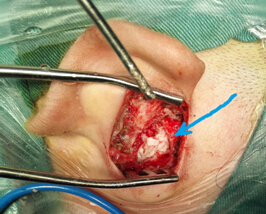

家屬帶患兒到市內(nèi)多家大醫(yī)院就診都告知手術(shù)風(fēng)險(xiǎn)較大,病灶難以一次性清除干凈?;純杭覍俦е囋嚳吹男膽B(tài)來我科就診,在我科主任及主治醫(yī)師詳細(xì)周密的診療計(jì)劃下,待炎癥控制后安排耳顯微外科手術(shù),一次性徹底清除留在患兒側(cè)顱底及中耳乳突腔內(nèi)的“定時(shí)炸彈”,并成功保護(hù)了患兒原有聽力,未出現(xiàn)面癱、耳后傷口感染及瘺口等術(shù)后并發(fā)癥,為我科耳顯微外科發(fā)展史上再添新亮。

3.術(shù)前CT2 4.術(shù)中術(shù)腔中的巨大膽脂瘤